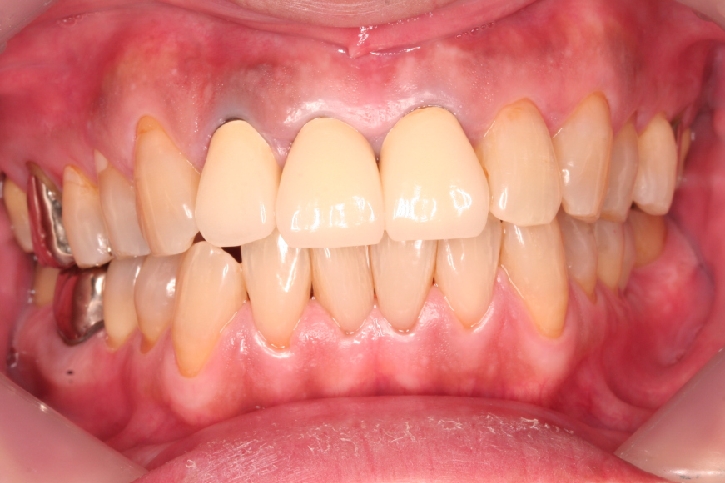

メタルセラミックス修復

担当歯科医師:川津良介理事長

2013年5月3日平成25年5月2日 千葉市中央区 H.S様 右下67番 メタルボンドクラウン修復